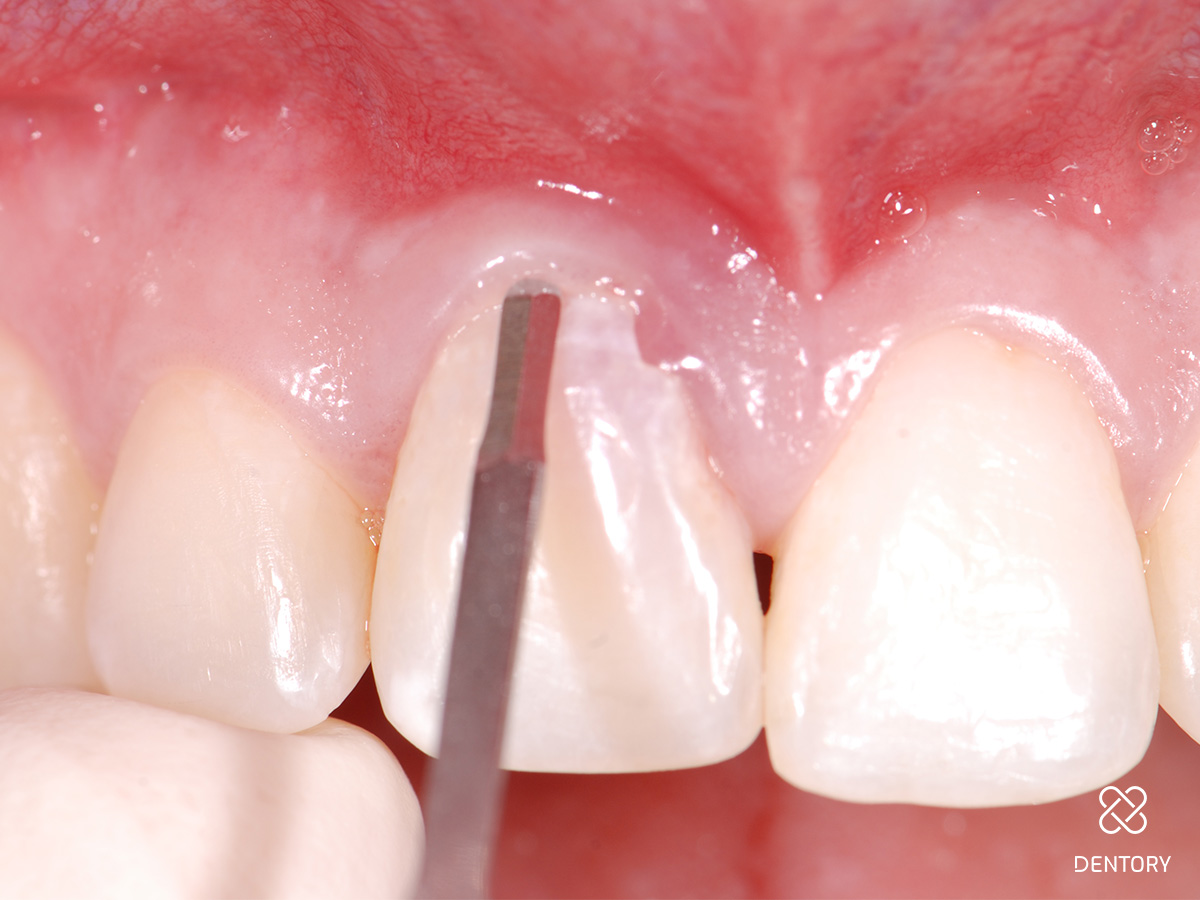

Abbildung 10

Eingenähter Punch vom seitlichen Gaumen: Die Entnahme kann im Prämolaren- oder Tuberbereich erfolgen.